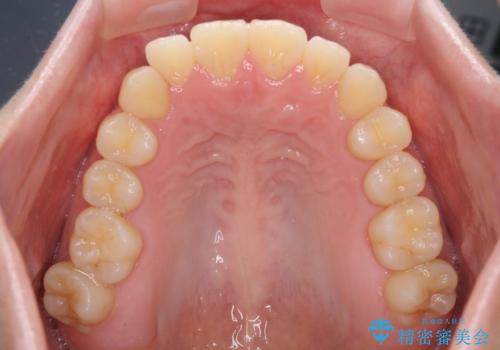

気になる前歯を整えたい インビザライン・ライトでの矯正治療

- ちょっとしたデコボコを整えたいとのことで来院された患者様です。

歯列不正は軽微であったため、インビザライン・ライトにより、費用を抑えて矯正治療を行うこととしました。

上下前歯の捻れが改善され、患者様には大変満足していただきました。